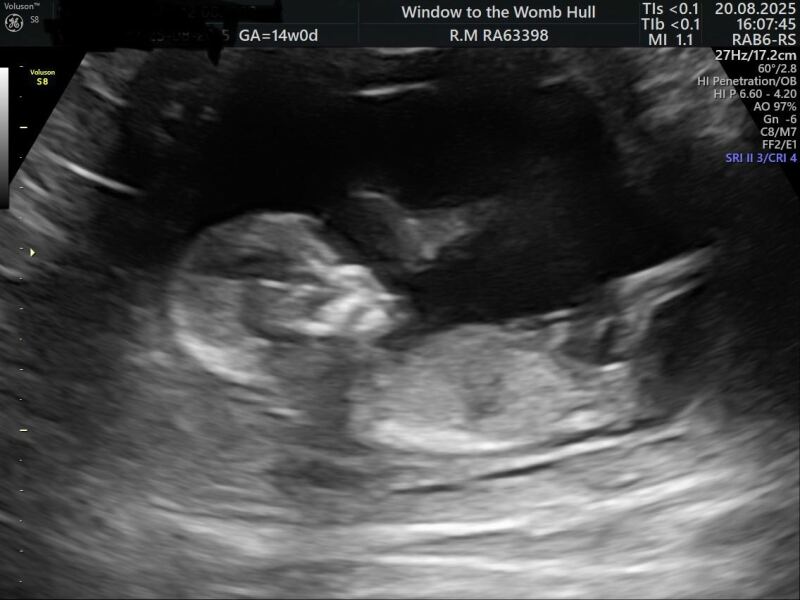

Hey @TheBroonOneAndTheWhiteOne bless you for checking in. I’m doing great. I’m 14w 1d with my little miracle. I still can’t quite believe it. I’m going for my gender scan next weekend but what do you think? We are pretty much nailed on it’s a girl

Line progress

OP posts:

Absolutely best news ever, @JLucyNick. I’m so glad you checked in; you deserve this. Are you enjoying it more or feel more relaxed now you’re past basically all of the difficult milestones? 😊

@EmPeEfthank you ❤️. im more relaxed than I was but I am still anxious and feeling like I need to have private scans but I think I will be like this all the way through x

TheBroonOneAndTheWhiteOne · 21/08/2025 17:53

Of course you're anxious after all you've been through!

I'm so happy to see your scan picture.